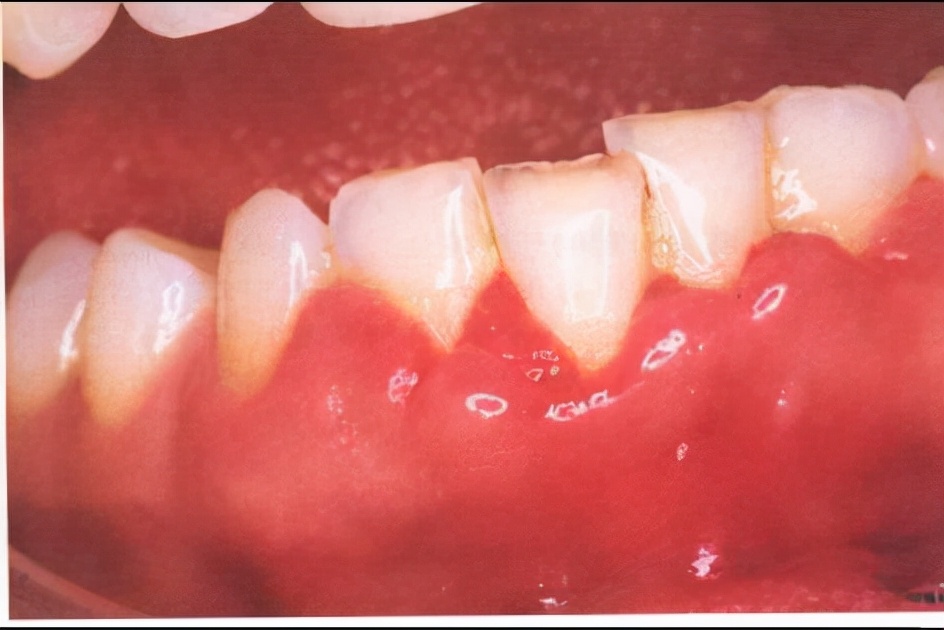

孕期牙龈出血可发生在少数牙或者全口牙,以前牙区为重。牙龈为鲜红或暗红色,有些严重者,出现牙龈肿胀、肥大,轻轻触碰即出血,进食时也容易出血。一般无疼痛,但严重者牙龈边缘可有溃疡形成甚至有口臭,有轻微疼痛感。

有些严重妊娠期牙龈炎会发展成牙龈瘤,即牙龈边缘出现牙龈包块,极易出血,严重时可妨碍孕妈进食或易咬破出血感染。孕妈分娩后,牙龈瘤会逐渐减小,但如果不去除牙结石等刺激因素是没法完全消除的,有的甚至需要手术切除。